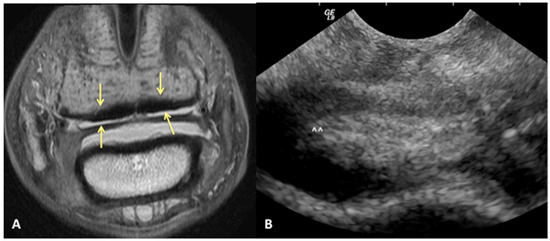

Results of sensitivity, specificity, and accuracy for comparisons of the findings of the DDFT, CSL, and navicular bursa are listed in Table 2. The low number of distal interphalangeal joint collateral ligament abnormalities resulted in low power for the statistic calculation, but prevalent findings are reported below. Ultrasound had the highest sensitivity for detecting enlargement and fiber damage of the dorsal aspect of the DDFT compared to identification of dorsal tearing of the DDFT on MRI, with a sensitivity of 85%, but it was less specific (60%) (Figure 1). Ultrasound was the least sensitive versus MRI to detect displacement (sensitivity 35%) of the CSL but was most specific for this finding (81%). Ultrasound also had a low sensitivity for detecting enlargement of the CSL (42%) but a specificity of 78% (Figure 2). Similarly, ultrasound was also less sensitive to detecting navicular bursa proliferation with a sensitivity of 47% but had higher specificity (78%) (Figure 3).

Figure 1. Transverse STIR MR image (A) and corresponding transverse US image (B), obtained at the level of the proximal recess of the navicular bursa. Palmar is on the top of the image, dorsal is on the bottom of the image, lateral is on the left. There is large area of bulging of the dorsal aspect of the lateral lobe of the deep digital flexor tendon (yellow arrows). All MR images are flipped to have the anatomy in the MR and ultrasound images in the same orientation.